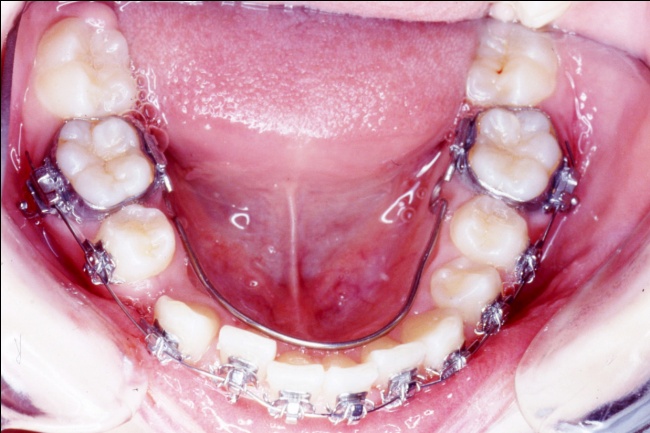

3 - L’art du contrôle en orthodontie

Le traitement a reposé sur des extractions ciblées et une mécanique orthodontique complexe, utilisant la méthode de Tweed avec ancrage maximal pour reculer les dents antérieures sans avancer les dents postérieures. Cette rétraction des blocs incisivo-canins a permis de repositionner les lèvres et d’harmoniser le profil. Un tel contrôle des mouvements dentaires est impossible avec de simples gouttières d’alignement, qui ignorent l’impact sur les tissus mous.